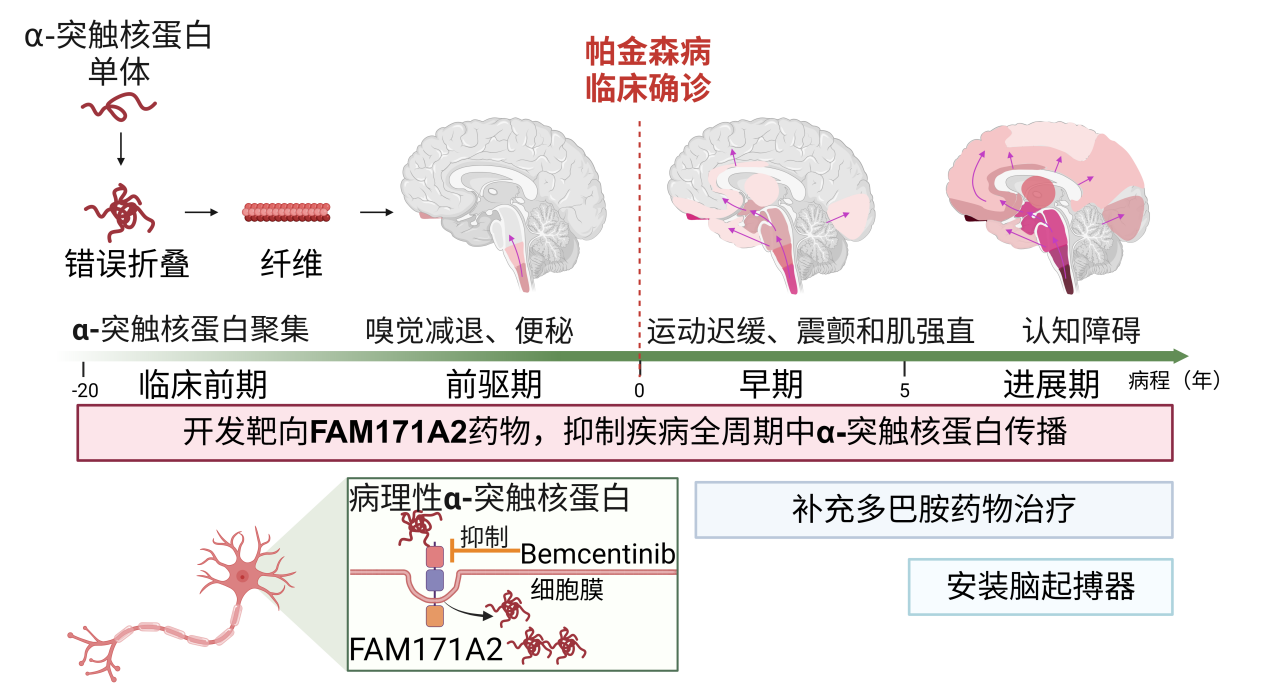

中国科学院生物与化学交叉中央刘聪团队复旦大学老师郁金泰团队、袁鹏团队联结,1A2是督促帕金森病发作繁荣的合节分子正在国际上初次揭示效力未知基因FAM17,疗价钱的幼分子化合物并筛选出拥有潜正在治,展带来新指望为延缓疾病进。2月21日颁发于《科学》合系考虑效果2025年。